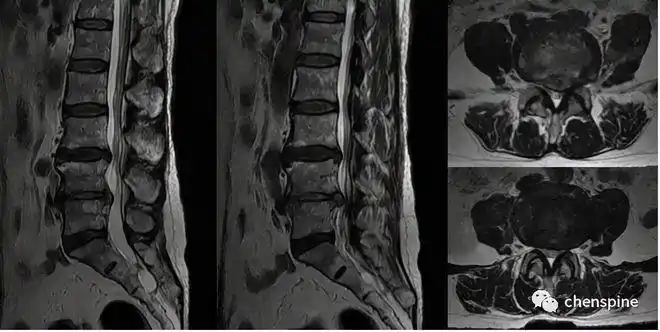

腰椎管狭窄常见问题解答